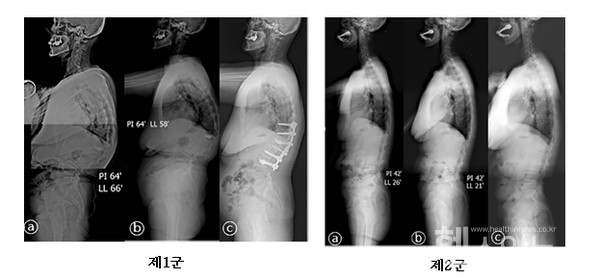

가톨릭대학교 서울성모병원 정형외과 김영훈(교신저자) 교수팀이 골다공증성 척추 골절 환자가 수술로 이행될 수 있는 위험요인, 즉 예측인자를 확인하기 위해, 골다공증성 흉요추 척추골절 환자를 조사하였다. 우선적으로 보존적 치료를 시행하였으나, 척추 변형이나 신경학적 증상으로 결국 수술이 필요했던 환자를 제1군, 보존적 치료로 성공적으로 치유된 환자를 제2군으로 나누어, 척추 X선 사진과 MRI 검사 소견을 비교하였다.

X선 시상면 지표를 확인한 결과, 척추가 앞으로 많이 굽어 있고, 골반이 앞으로 많이 틀어져 있는 환자가 제1군에서 높은 비율을 차지하였다. 즉 척추 X선의 시상면 지표로 골다공증성 골절의 보존적 치료가 성공 했는지 확인할 수 있음을 증명하였다. ※ 그림1